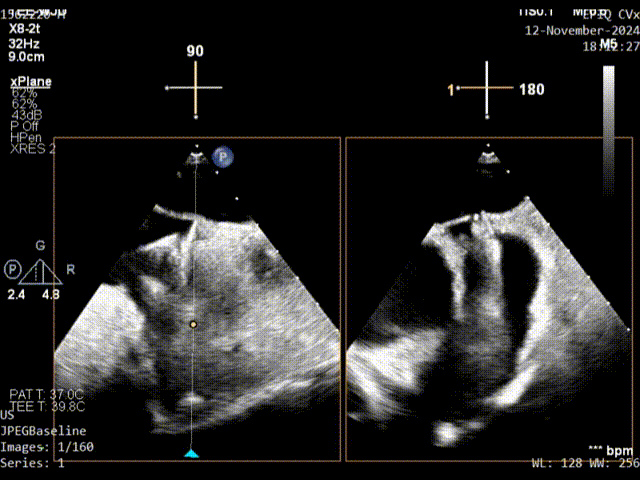

继发隔缝合

原发隔第一针缝合